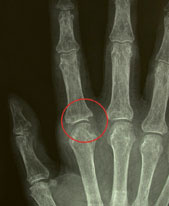

Abb. 2 und 3

Rheumatoide Arthritis (Polyarthritis). Die Fingergrundgelenke und das Handgelenk sind deutlich geschwollen. Der fortgeschrittene Befall kann zu zunehmender Deformierung sowie zur Fehlstellung dieser Gelenke führen.

hirslanden-was-ist-eigentlich-rheuma-3

Durch den entzündlichen Gelenkbefall kommt es zu Erosionen des Knochens, hier vor allem im Bereich des Zeigefinger-Grundgelenkes.

Entzündlicher Rheumatismus: Entzündlich-rheumatische Krankheiten können durch Störungen im Immunsystem (wie bei den Autoimmunkrankheiten), durch Infektionen oder durch Kristallablagerungen in Geweben hervorgerufen werden. Oft sind die Ursachen und Auslöser unbekannt. Erbfaktoren spielen eine wichtige Rolle. (Abb. 2 und 3)